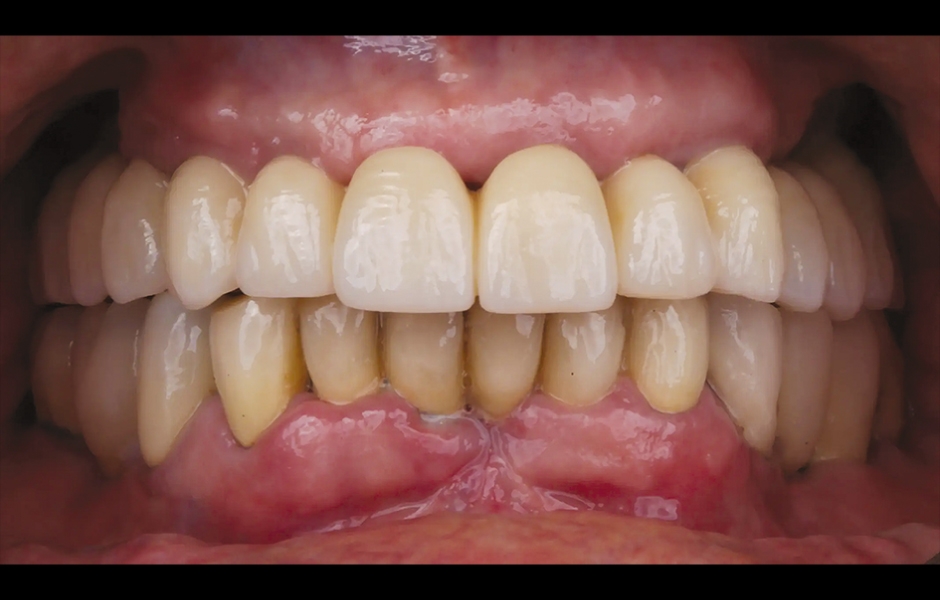

Při finální návštěvě byla nasazena definitivní hybridní šroubem fixovaná protetika. Definitivní práce sestávala z CAD/CAM titanového skeletu přišroubovaného na všechny implantáty a tří monolitických zirkoniových segmentů vlepených nahoře (obr. 18a–c). Byla zkontrolována okluze a pacient byl zařazen do čtyřměsíčního recall programu. Při poslední kontrole (rok po implantaci) byly všechny implantáty úspěšné a pacient byl plně spokojen s novou protetikou (obr. 19–22).

Obr. 19: Definitivní protetická práce při jednoroční kontrole, frontální pohled.